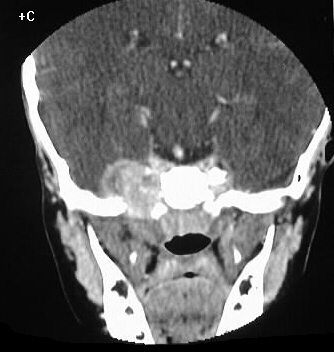

, 19. Rhabdomyosarcoma. (18) Axial Pelvic CT Scan Obtained With

www.researchgate.net

www.researchgate.net